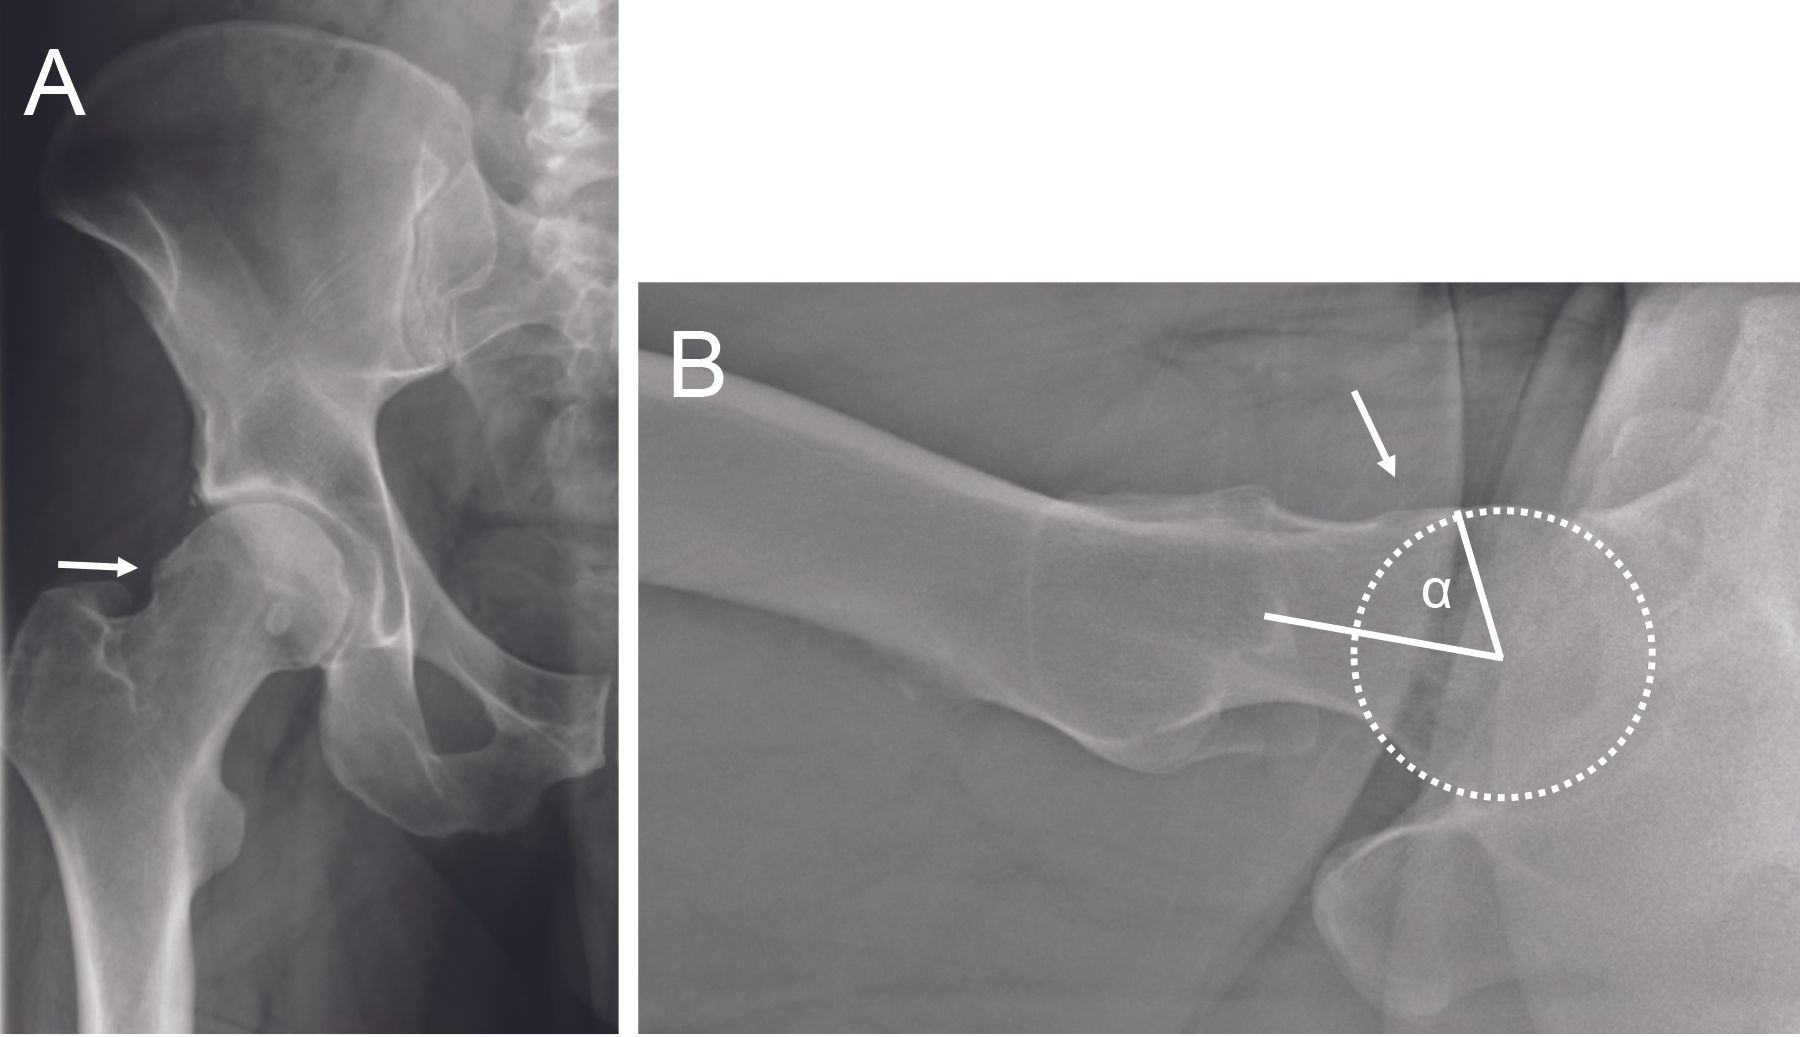

The retroversion of the acetabulum may be focal (<30%) or global (>30%) depending on the crossing sign size. Posterior wall sign (posterior wall medial to the center of the femoral head), and ischiatic spine sign (visible on front pelvic film beyond the iliopubic line) are the two other signs for acetabulum retroversion. The filling of the cervico-cephalic junction can cause a cam effect (Figure 5), sometimes with a pistol grip appearance. The cam effect can be quantified using the alpha angle measured on the axial radiograph.

Finally, radiographs can exclude the presence of advanced arthritic changes, for which conservative hip surgery is no longer appropriate, and arthroplasty options should be considered. Arthro-MRI is the imaging procedure of choice for assessing the labrum and cartilage. Injection of contrast material into the hip joint allows better visualization of the labrum and cartilage. Lesions of the labrum (Figure 6) are most often found in the anterosuperior part of the joint. MRI with radial reconstructions allows better localization and quantification of the cam effect morphology (Figure 7). The alpha angle can also be measured on this imaging modality.